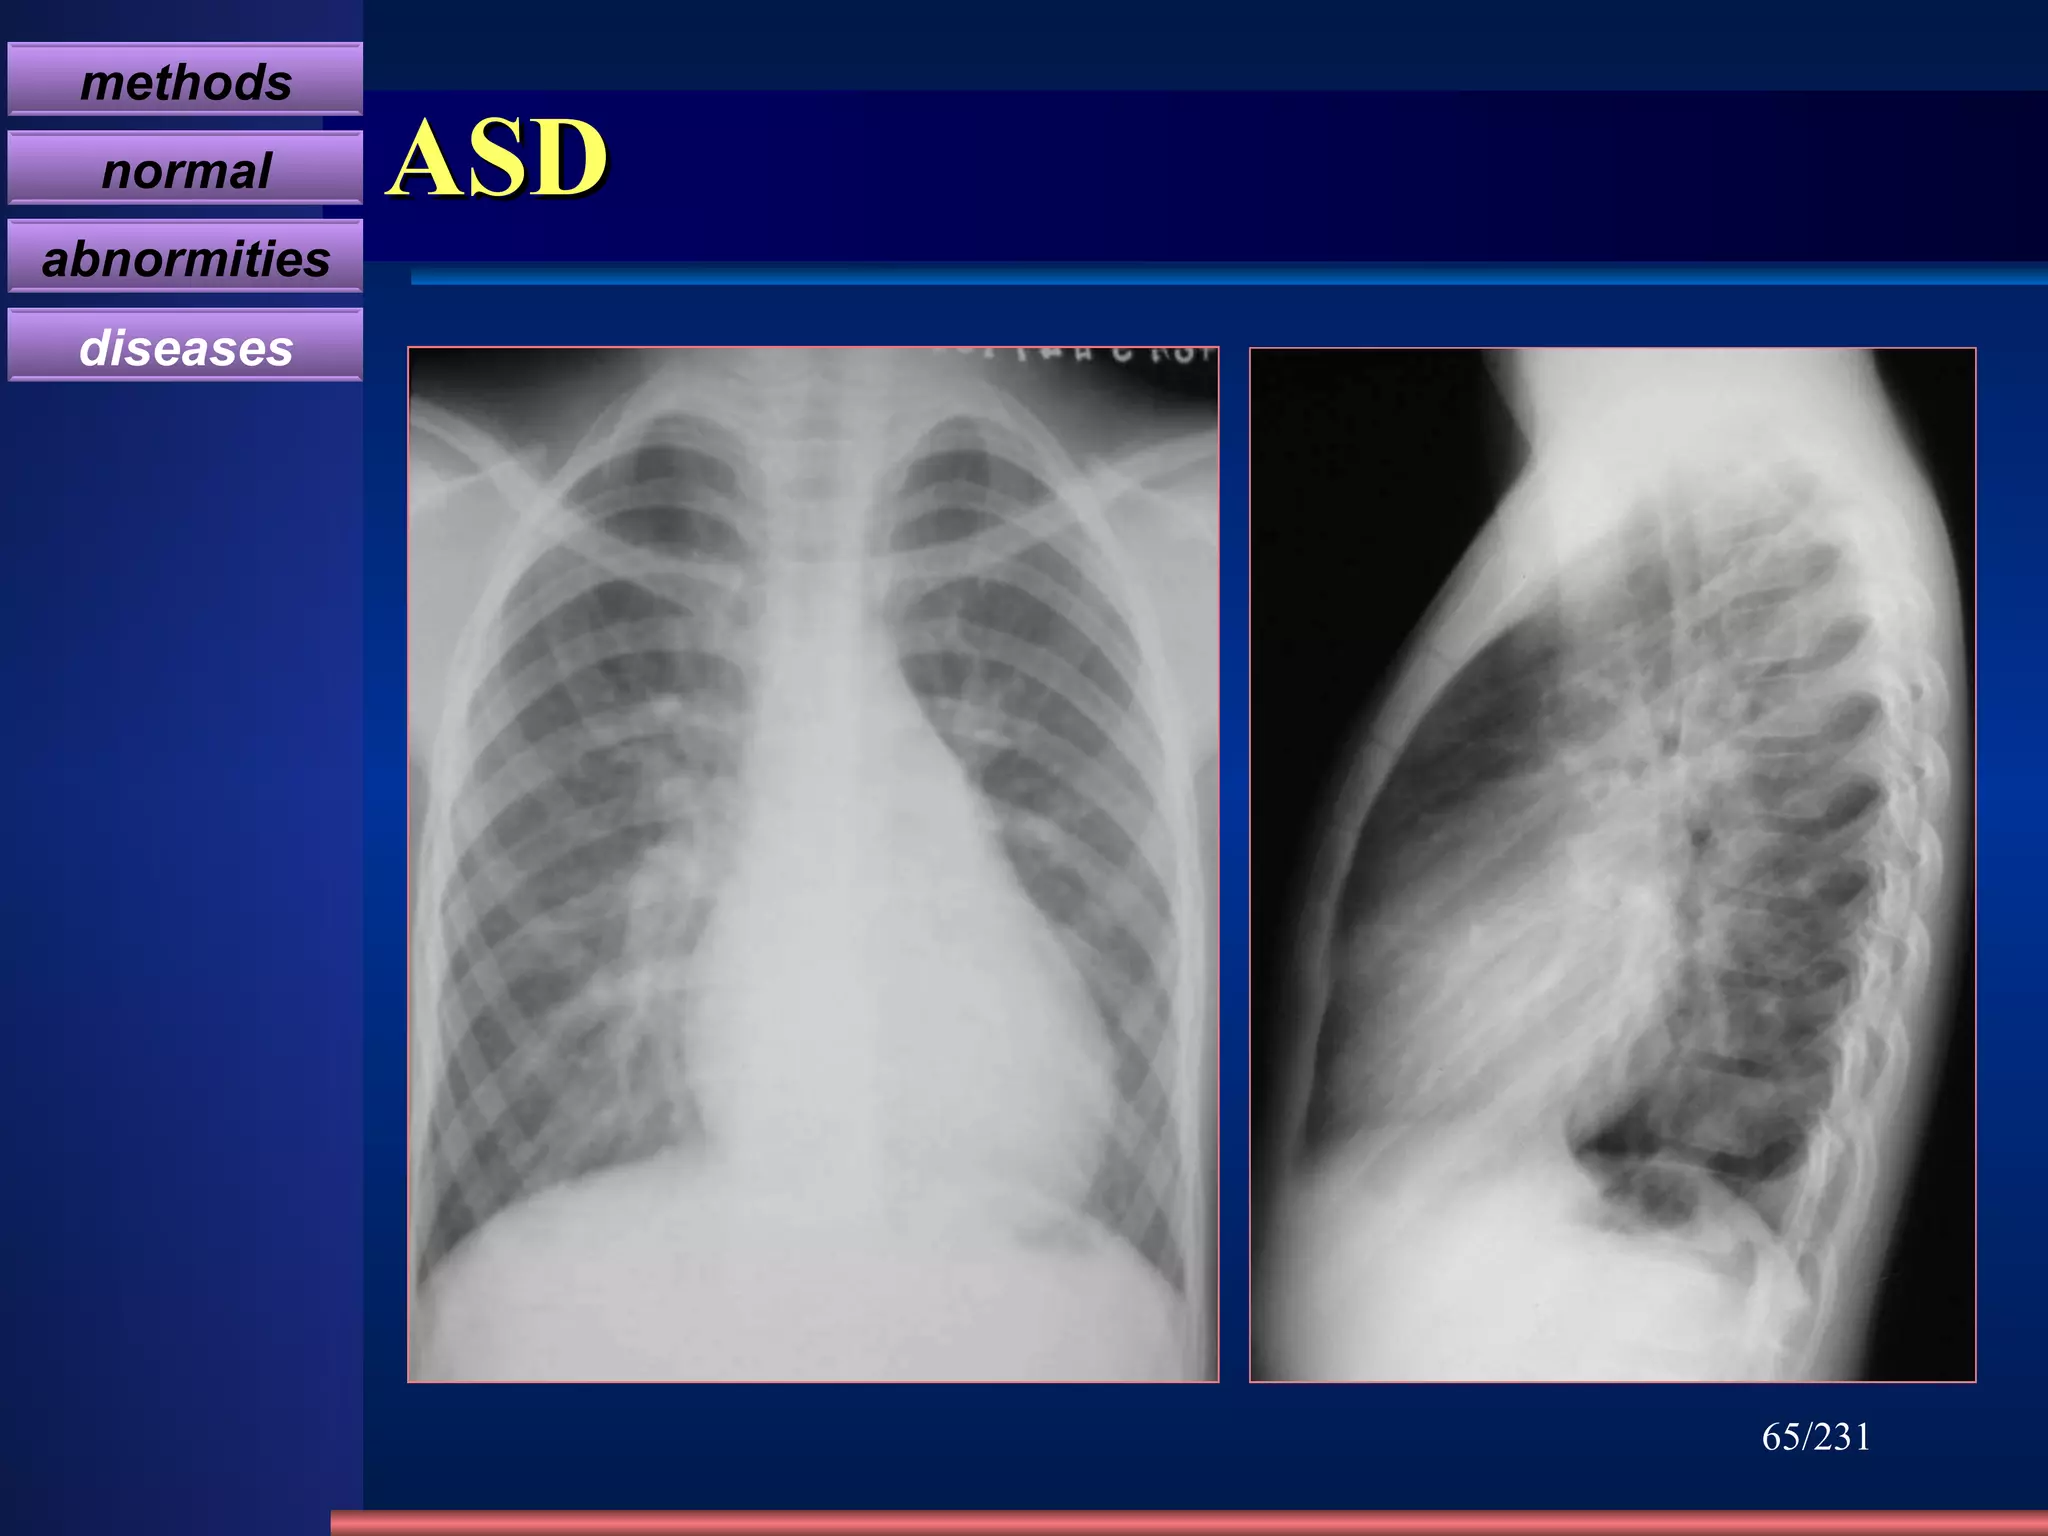

ASD Clinic mostly adult  SM on the 2th-3rd intercostal of the left sternal border Change of hemodynamics X-ray appearance Cardiomegaly , “mitral configuration” RA & RV↑ ,  RA↑ ↑   obviously Pulmonary artery segment bulge  , hilum angiectasia, hilum dance pulmonary blood flow↑ ↑. PAH in later stage LA do not enlarge, LV and aorta shrink /231 4 type: Ostium primum , ostium secundum Sinus venosus , coronary sinus Fossa Ovalis defect 80~90% Atrial septal defect methods normal abnormities diseases

ASD Prominent pulmonary vessels Prominent MPA Normal left atrium